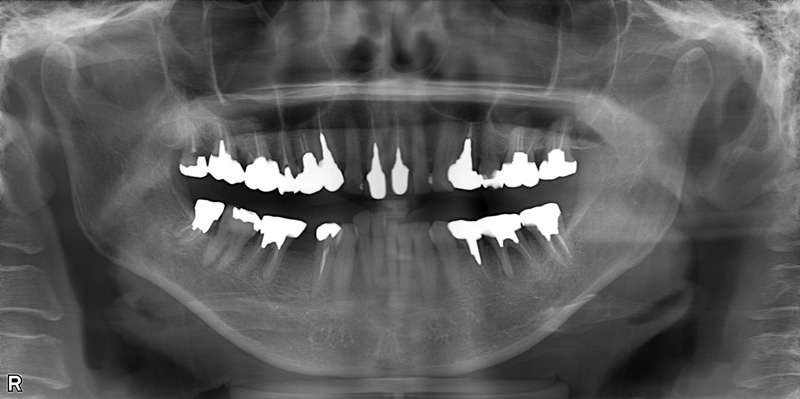

71歳女性

治療前

治療後

| 施術名 | インプラント治療 インプラントオーバーデンチャー治療 |

| 施術の説明 | インプラント治療とは、歯を抜いた所にチタン製の人工歯根を埋入し、新しく歯を入れる方法です。上顎は、入れ歯の支えとしてインプラントを使用しています。 |

| 施術の副作用 (リスク) | 腫れや疼痛を感じる、違和感を感じるなどの症状を生じることがあります。 |

| 施術の価格 | 120万円~+消費税 |